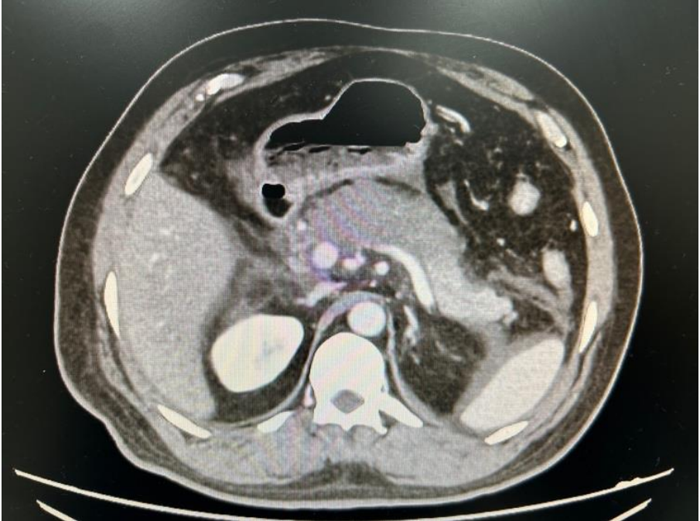

Paciente masculino, 54 anos, apresenta dor abdominal intensa irradiada para o tórax e dorso, com intensidade 10/10, associada a náuseas, porém sem vômitos. Ao exame físico, encontra-se afebril, anictérico, com PA 166x121 mmHg, FC 78 bpm, abdome globoso, tenso, doloroso difusamente, com ruídos hidroaéreos diminuídos.

Exames laboratoriais: Hb19,4 g/dL, leucócitos 21.930/mm³, creatinina 2,81 mg/dL, ureia 92 mg/dL; bilirrubina total 1,45 mg/dL, bilirrubina direta 0,38 mg/dL, fosfatase alcalina 49 U/L, GGT 37 U/L, amilase 2234 U/L, lipase 2984 U/L, PCR 44 mg/L (VR<1,0). Aferida pressão intrabdominal 17mmHg.

Realizada tomografia computadorizada para diagnóstico diferencial e obtida a imagem abaixo:

Considerando o diagnóstico do paciente, a conduta imediata deve ser: